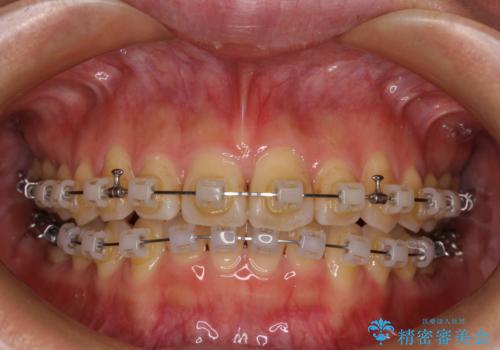

- クリアブラケット

- 1年

僅か1年間できれいに歯列を整えることができ、患者様には大変満足していただきました。